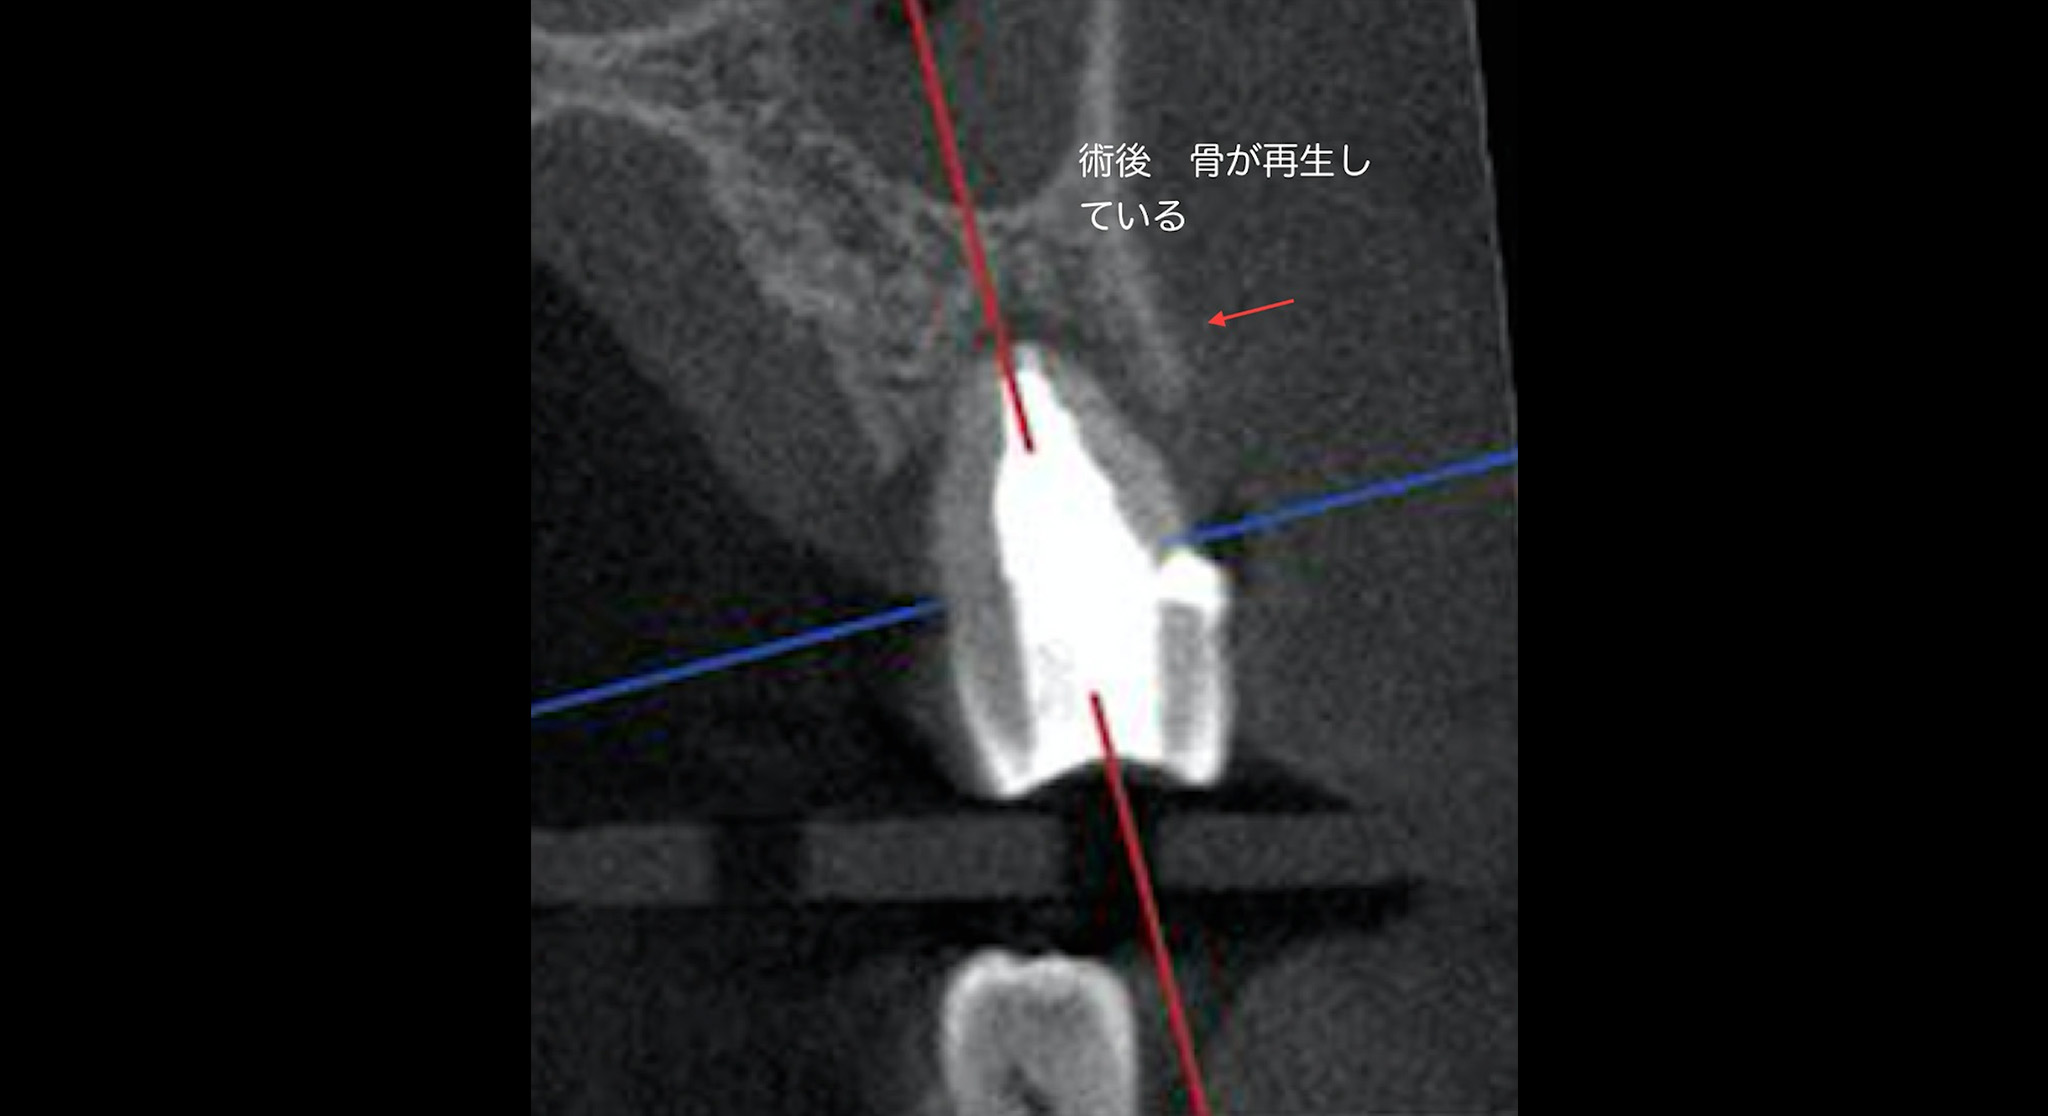

根の先にから約3mmの部分でカットして根の尖端を除去しています。術後3ヶ月なので骨が完全に再生されていませんが治癒傾向を認めます。(今後、骨はより多く再生されると思います)この歯の奥にインプラントを埋入予定なので、この歯の炎症を放置してインプラントは入れられません。

- 歯周病の検査でポケットを測定する時に歯周ポケットがあるからといって必ず歯周病だと診断することは危険です。その理由は歯の内部が細菌感染を起こしてその結果、根の先に膿がたまり膿は組織の弱いところから外に出ようとするために歯と骨の間にある歯根膜という部分から外に向かって排膿しようとして歯周組織が破壊され、あたかも歯周ポケットを形成するように見えるからです。つまり歯周ポケットがあるからといって必ずしも歯周病ではないということになります。もし、診断を間違えて歯周病の治療であるポケットを綺麗にする掻爬術を行ったとすると、歯の表面にあるセメント質を剥ぎ取ってしまうので歯周組織である歯根膜・骨は二度と再生致しません。そのような意味で診断がとても重要になります。こちらの患者様は歯頚部に力により欠損が出来てそこから歯の内部に細菌感染がおこり歯髄がダメージを受け根先端が化膿して排膿を起こして歯周ポケットのような排膿路が出来た症例です。2.5ヶ月にCTを撮影して治癒を確認致しました。骨が見事に再生していることに注目して下さい。根管治療が成功した結果、排膿路が消え歯周ポケットがなくなりました。